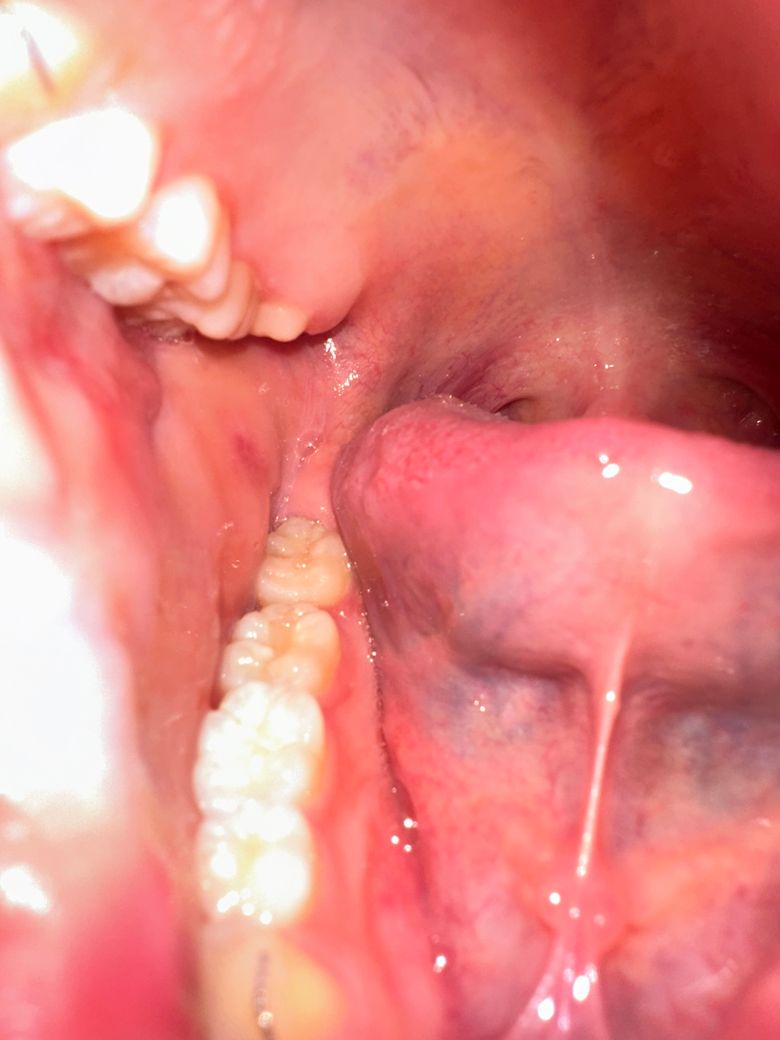

제가 불안한 부분은 첫번째 사진에 볼 점막쪽 돌기들과 피점? 같은 것, 어금니 충치와 두번째 사진 볼 점막의 빨간 부분과 돌기, 충치입니다...

구강암, 충치 등 사진상의 의심 소견을 알려주세요 ㅠㅠ

구강 상태가 특별히 문제가 보이지는 않는 것 같습니다. 구강암을 의심할만한 소견은 안보입니다.

씹어서 생긴 상처, 혈종의 흔적일 수 있을 것 같습니다 큰 문제는 없어보입니다

우선 사진상으로 봤을 때 충치는 보이지 않습니다. 양쪽 볼에 볼록 튀어나온 것은 Stensen duct로 귀밑샘(이하선)의 침 분비구로 보이고 그것이 아니더라도 종종 볼을 씹어서 그랬을 가능성이 높습니다. 빨간 부분과 피 점도 씹어서 그랬을 가능성이 높습니다. 전반적으로 충치나 잇몸 염증은 없어보이고 사랑니도 굉장히 가지런하게 맹출되어서 딱히 문제가 될만한 부분은 없어보입니다.